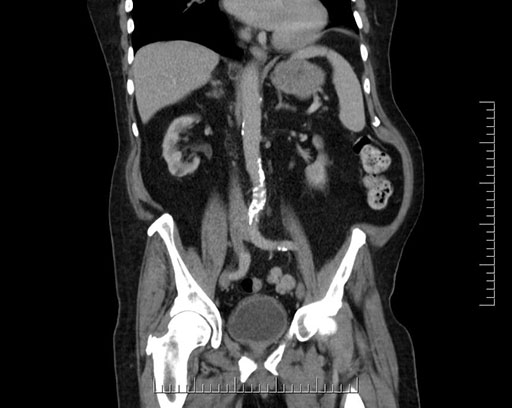

Whipple (pancreaticoduodenectomy) [case 7]

Imaging Analysis

Look through the patient's CT scan to identify any areas of concern for the necessary procedure.

Based on your CT findings, which issue(s) would give reason for "planned slowing down moment(s)" in this case?

Considering a standard Whipple procedure, what step(s) of the operation would you do differently in this case?